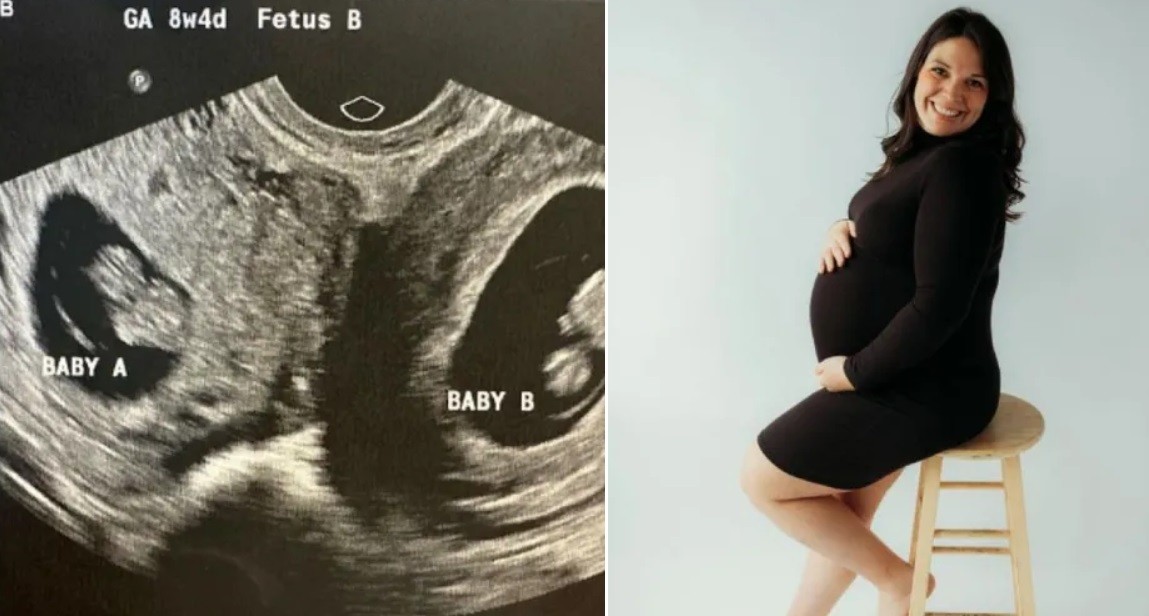

Durante un ultrasonido de rutina en mayo, la masajista terapéutica y madre de tres hijos, se enteró no solo de que esta vez tendría mellizos, sino que cada feto estaba presente en cada uno de sus úteros.

"Lo que probablemente sucedió es que ovuló de manera separada y un óvulo bajó por cada trompa de Falopio, es decir, bajó a cada lado del útero, y luego los espermatozoides viajaron hacia cada útero por separado y la fertilización se produjo separadamente", dijo en declaraciones televisivas Shweta Patel, la ginecobstetra que atiende a Hatcher en el Centro de Mujeres e Infantes de la Universidad de Alabama, en Birmingham.

Los embarazos en ambos úteros son extremadamente inusuales. A Hatcher le dijeron que las posibilidades eran de 1 en 50 millones, siendo el caso más reciente el de una mujer en Bangladés que, a los 20 años, dio a luz a mellizos con una diferencia de 26 días entre ambos nacimientos.